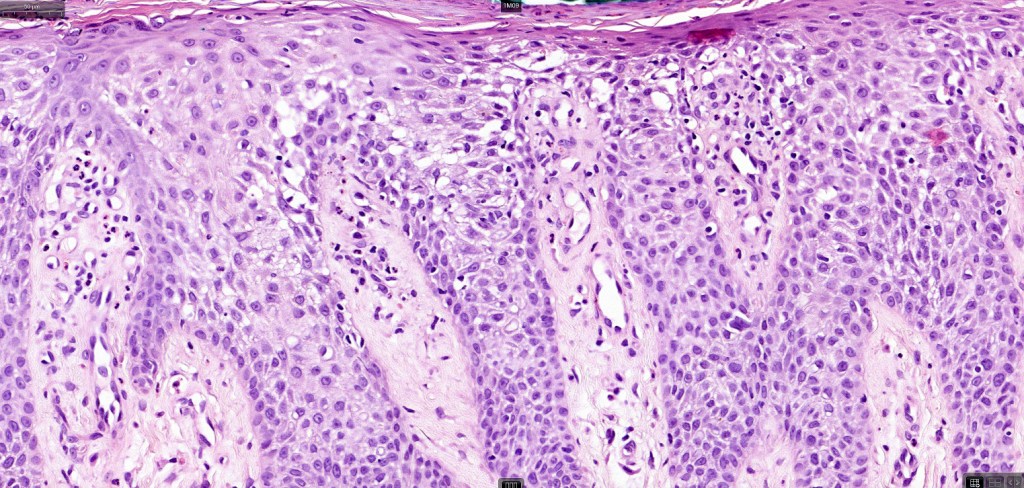

Histological features

•Parakeratotic scale with neutrophils

•Sharply demarcated acanthosis/psoriasiform hyperplasia; bland epithelium

•Fusion of rete ridges

•Cytoplasmic pallor or clear cell change; spongiosis sometimes present

•Characteristic intraepidermal adnexal epithelial sparing

•Dendritic melanocytes sometimes present

•Vascular dilatation in the dermal papillae and a perivascular sometimes neutrophil-rich infiltrate